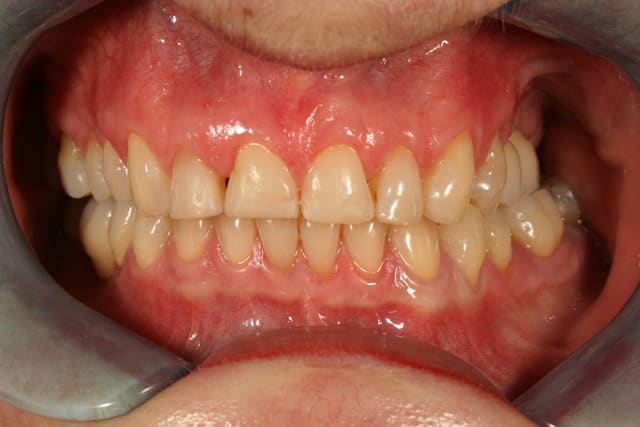

voilà le resultat collé

je suis resté trop supragingival, mais la patiente est très contente (ouf, c'est l'essentiel !)

elle a sa gouttière pour la nuit

E carteurs yiazkj - Eugenol

Sourire w9qjjh - Eugenol

Occlusal jyrk8g - Eugenol

Zooom bjj8ay - Eugenol